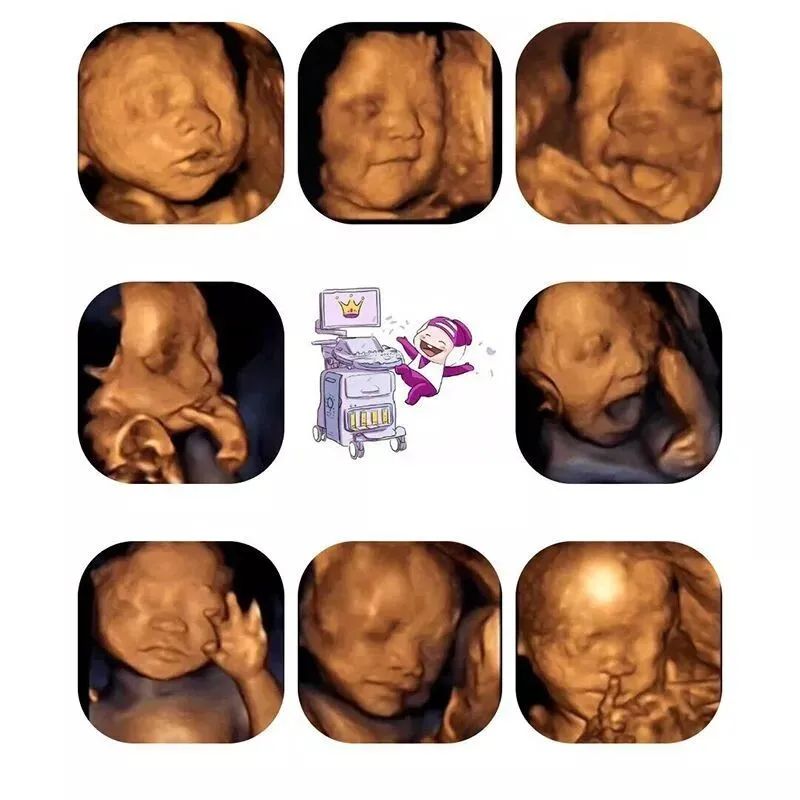

超声影像(四维彩超)除了能让宝爸宝妈提前跟未出生的宝宝“见面”,它ZUI主要的功能是对胎儿进行各种检查,及早发现胎儿生长中出现的问题,如唇裂、脊柱裂等。另外,四维彩超的图像显示比传统彩超、B超更清晰、更准确。

查看胎儿的活动:可以检查到胎儿在宫内是否缺氧,肢体运动、胎儿的吞咽动作等,能够很好的看到胎儿在母体内的活动状况。

此时胎儿已经基本发育成形,局部结构和运动状态都可以清晰地观察到,可发现胎儿发育异常,比如无脑儿、脊柱裂、内脏外翻、单腔心、致死性软骨发育不良等。